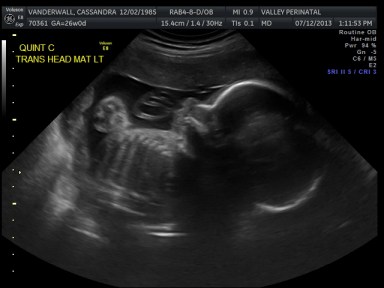

Friday we surpassed yet another milestone! The babies have been cooking for 7 months, which means we are now above the average gestational age for quintuplets. All of the babies were measured on Friday and they are all measuring within a day or two of the recommended size for babies at this point in pregnancy.

The biggest one in the bunch is Baby B at 2lbs and 12oz at the 62nd percentile. Little Elle Rose (Baby E) is the munchkin, but not by much as baby D and Theo (baby A) are also the same weight (2 ½ lbs) but just a bit longer. At this rate, when the baby’s are measured again at 32 weeks they will be about 1lb heavier each. Let’s just hope this Mama can keep up!

All of their organs (kidneys, bladders, hearts, brains, stomachs) look great and are also appropriate sizes. The blood flow to Elle has improved and has stabilized. All heart rates remain within normal limits, and are often on the higher side, which is probably because they just can’t sit still. We are truly excited to meet our little wiggle worms!